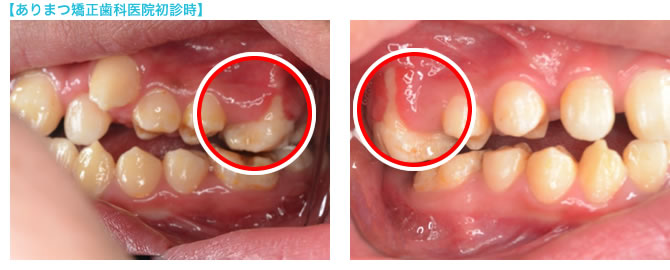

下記の症例はJBO認定専門医のありまつ矯正歯科医院へ初診で訪れた患者さんのものです。

- ご相談の患者さん(16歳10ヶ月 男性)

- 前医での治療期間:2年以上

治療内容:出来る限り歯は抜きたくないという母親の思いから、「永久歯を抜かないで、矯正治療が出来る」という医院で拡大治療を開始。あごの骨を大きくするため、拡大装置を治療中ずっと装着していたとのこと。 - ご相談の理由

- 2年以上拡大治療を行ったがあまり改善が認められず、突然次回よりマルチブラケット(いわゆるワイヤーを使う矯正装置)による治療に切り替えますと言われた事に不信感を持って、JBO認定専門医のところに相談にこられました。

- 患者さんの状態

- 上顎の第一大臼歯のほっぺた側の歯根が露出していました。(※上部画像の赤丸部分)

JBO認定専門医が指摘したところ、前医からの説明や指摘は全くなかったそうです。

過度な拡大治療が行われていたことがわかります。